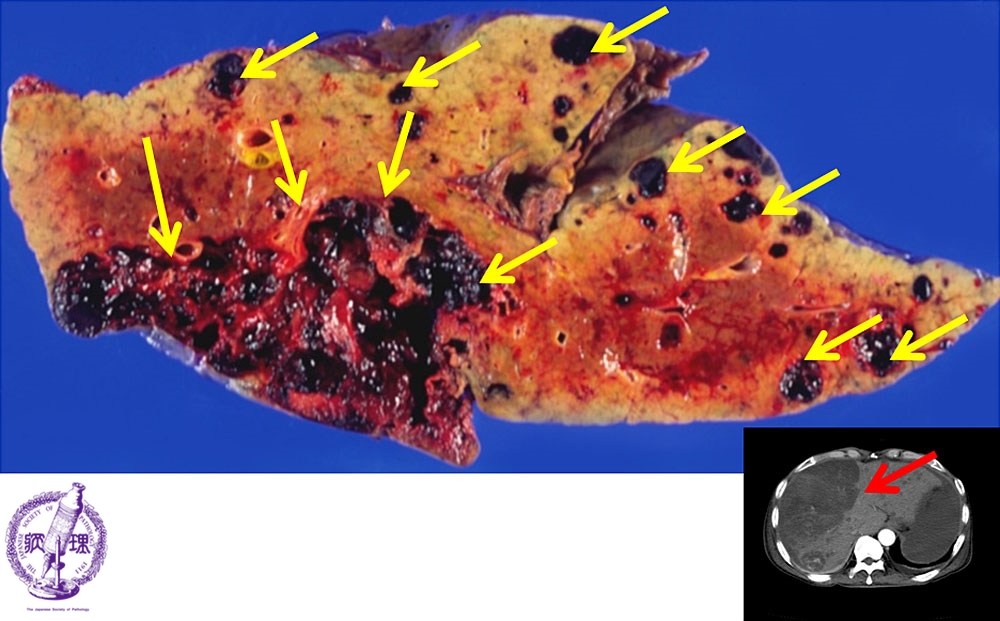

- ★(14)Angiosarcoma of the liver

Macroscopic image: There is sponge-like tumor which contains reddish-brown thrombus (yellow arrows) and demonstrates an expansive, obscure boundary.Right lower: In the CT image, the low-density area (black color) corresponds to tumor (red arrow).